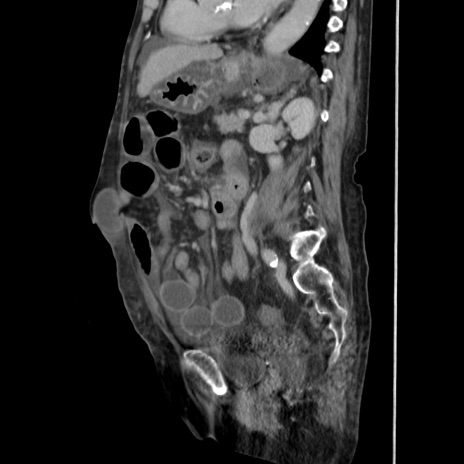

症例31(矢状断像)

【症例】80歳代 女性

【主訴】腹部膨満感

【現病歴】他院にて肝硬変にてフォロー中。1週間前から便秘、腹部膨満感、臍部腫瘤あり受診となる。

【既往歴】肝硬変

【身体所見】腹部膨隆あり、皮膚変化なし、疼痛なし。

【データ】WBC 4600、CRP 0.25